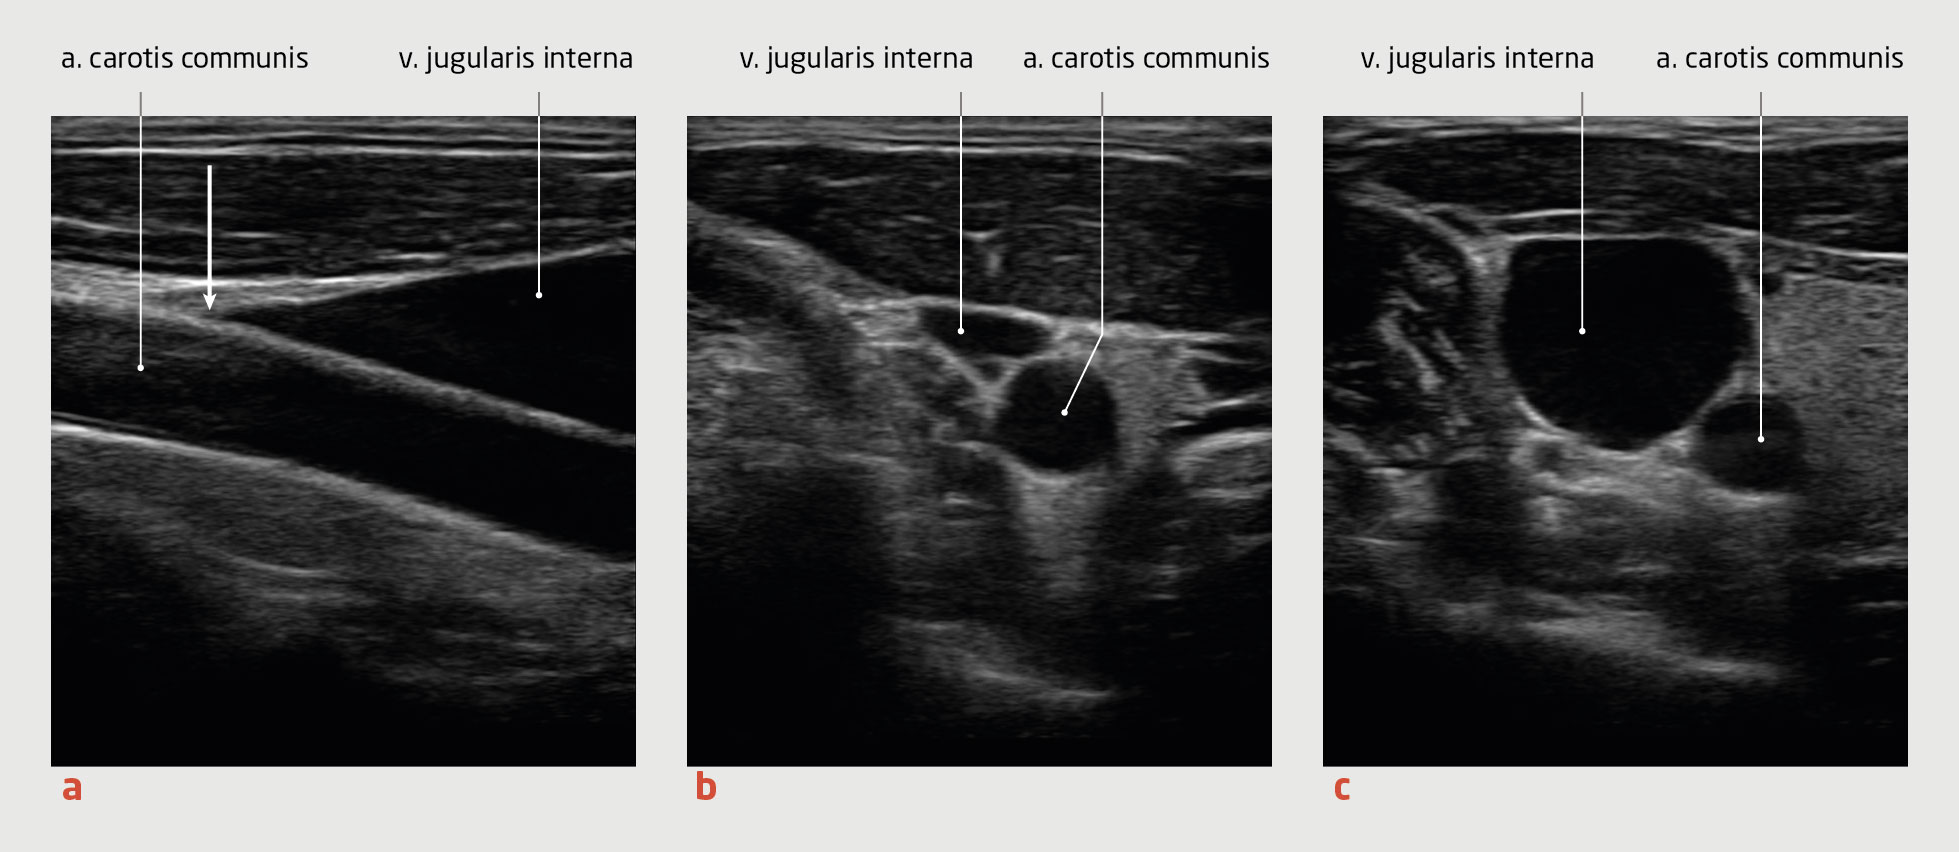

• Het combineren van conventionele methoden met eenvoudig toepasbare point-of-care-echografie (POCUS) helpt om de vullingsstatus nauwkeuriger vast te stellen. Bij dit POCUS-onderzoek beoordeelt men het punt van collaps van de v. jugularis interna, de diameter van de proximale v. cava inferior en de aanwezigheid van pulmonale B-lijnen.